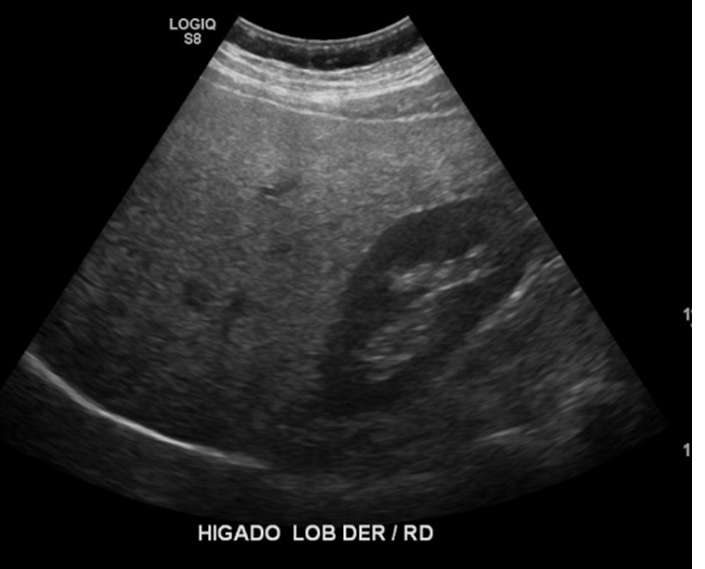

Examen limitado por meteorismo. Páncreas parcialmente visualizado. Hígado aumentado de ecogenicidad con área de respeto periportal sugerente esteatosis difusa moderada. En región dolorosa en FII se observa imagen pseudonodular hipoecogénica, con aumento de ecogenicidad de la grasa adyacente, sin relación intestinal evidente, sugerente apendagitis epiploica.

Hallazgos ecográficos sugerentes de apendicitis epiploica a nivel del flanco izquierdo. Cambios de esteatosis hepática leve. Resto del estudio ecográfico abdominal sin hallazgos significativos.